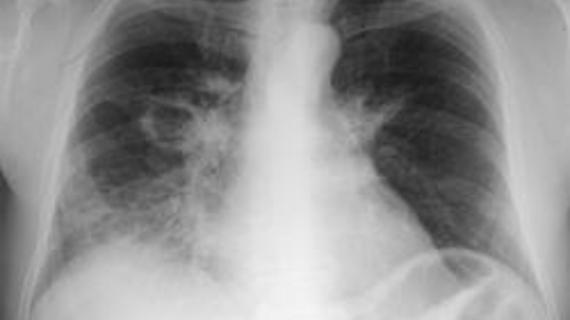

Бессимптомную пневмонию очень сложно распознать. У больного нет ни кашля, ни температуры. Указывающими признаками болезни могут быть общая слабость, хрипы...

Чтобы эффективно лечить пневмонию у взрослых, необходимо провести тщательное обследование пациента. Лекарства подбираются врачом с учётом типа возбудителя болезни и...